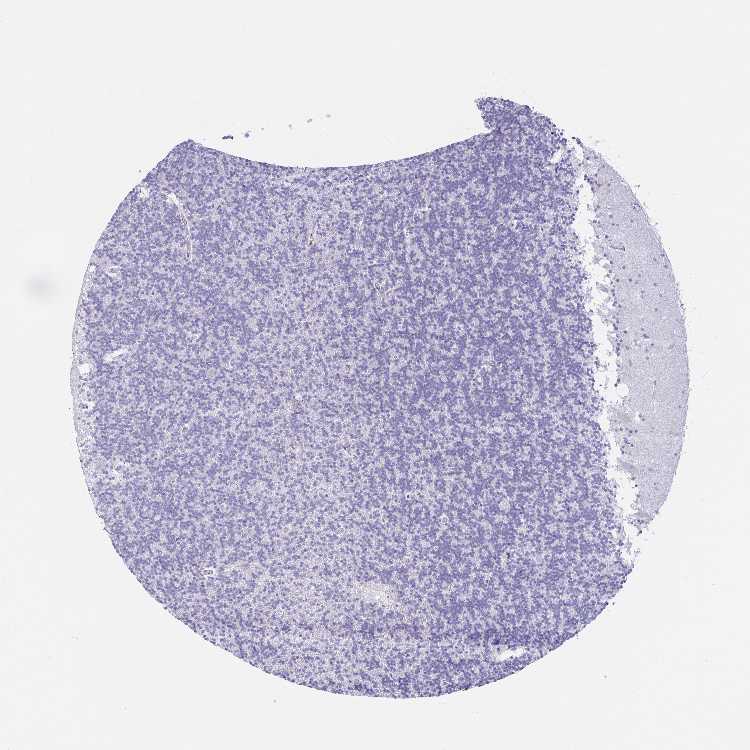

CEREBELLUM - Antibody stainingi

Antibody staining in the annotated cell types in the current human tissue is reported as not detected, low, medium, or high, based on conventional immunohistochemistry profiling in selected tissues. This score is based on the combination of the staining intensity and fraction of stained cells.

Each image is clickable and will lead to virtual microscopy that enables deeper exploration of all samples and also displays staining intensity scores, fraction scores and subcellular localization as well as patient and tissue information for each sample.

Antibody HPA054577

Purkinje cells Not detected

Cells in granular layer Not detected

Cells in molecular layer Not detected